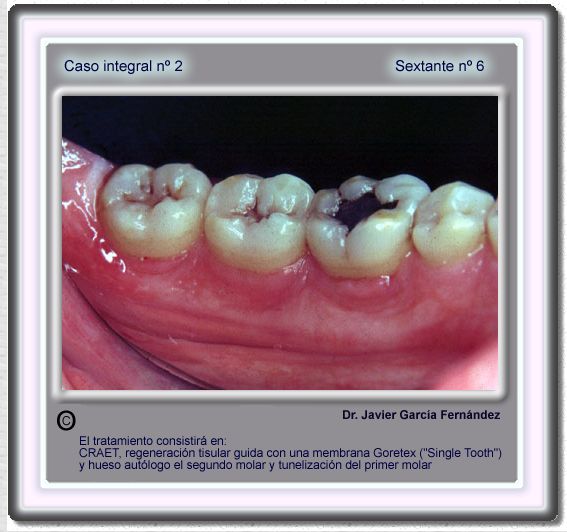

image 75